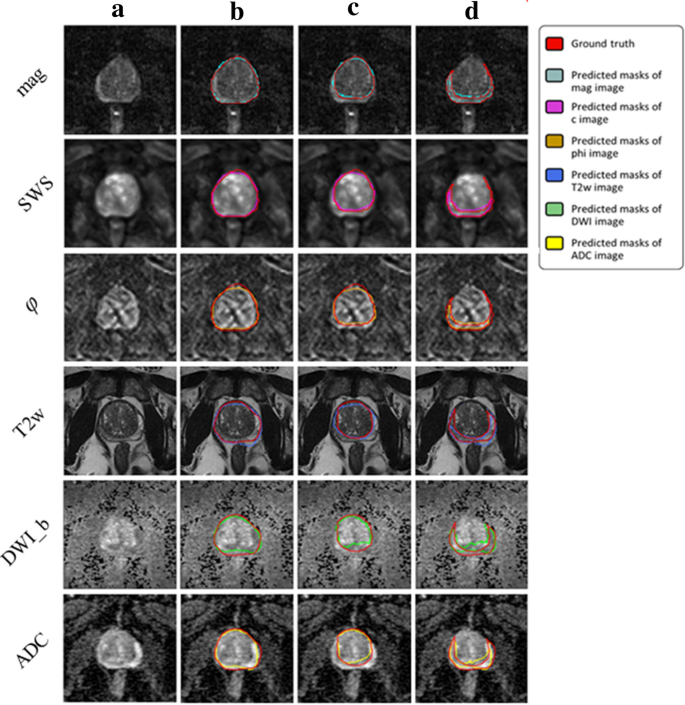

Figures 5 and 6 illustrate segmentation results for each of the two training approaches. The boundary of automatically segmented regions closely follows the boundary of manual segmentations.

Our experimental results for IMs trained on different combinations of maps showed that the proposed method was capable of efficiently segmenting PG, CZ, and PZ from the input MRI/MRE images. DS ranged from 0.87 ± 0.04 (ADC) to 0.93 ± 0.04 (mag), from 0.85 ± 0.09 (DWI_b) to 0.95 ± 0.03 (mag), and from 0.53 ± 0.10 (ADC+DWI_b) to 0.77 ± 0.05 (mag), for PG, CZ, and PZ, respectively. Also, HD was minimized (i.e., best contour consistency) based on mag with 0.86, 0.76, 0.98 mm (Fig. 5 and Table 2). However, performance differences between MRE (mag, SWS, \(\varphi\)) and MRI maps (T2w, DWI_b, ADC) were statistically not significant except for CZ, where MRE (mag, SWS, \(\varphi\)) had a significantly higher DS than MRI (T2w, DWI_b, ADC, p<0.05).

Examples of segmentation results achieved with IMs: first column (a) shows the original image, second (b), third (c) and forth column (d) show masks of prostate, central and peripheral zones, respectively.

Examples of segmentation results achieved with the UM: first column (a) shows the original image, second (b), third (c) and forth column (d) show masks of prostate, central and peripheral zones, respectively.